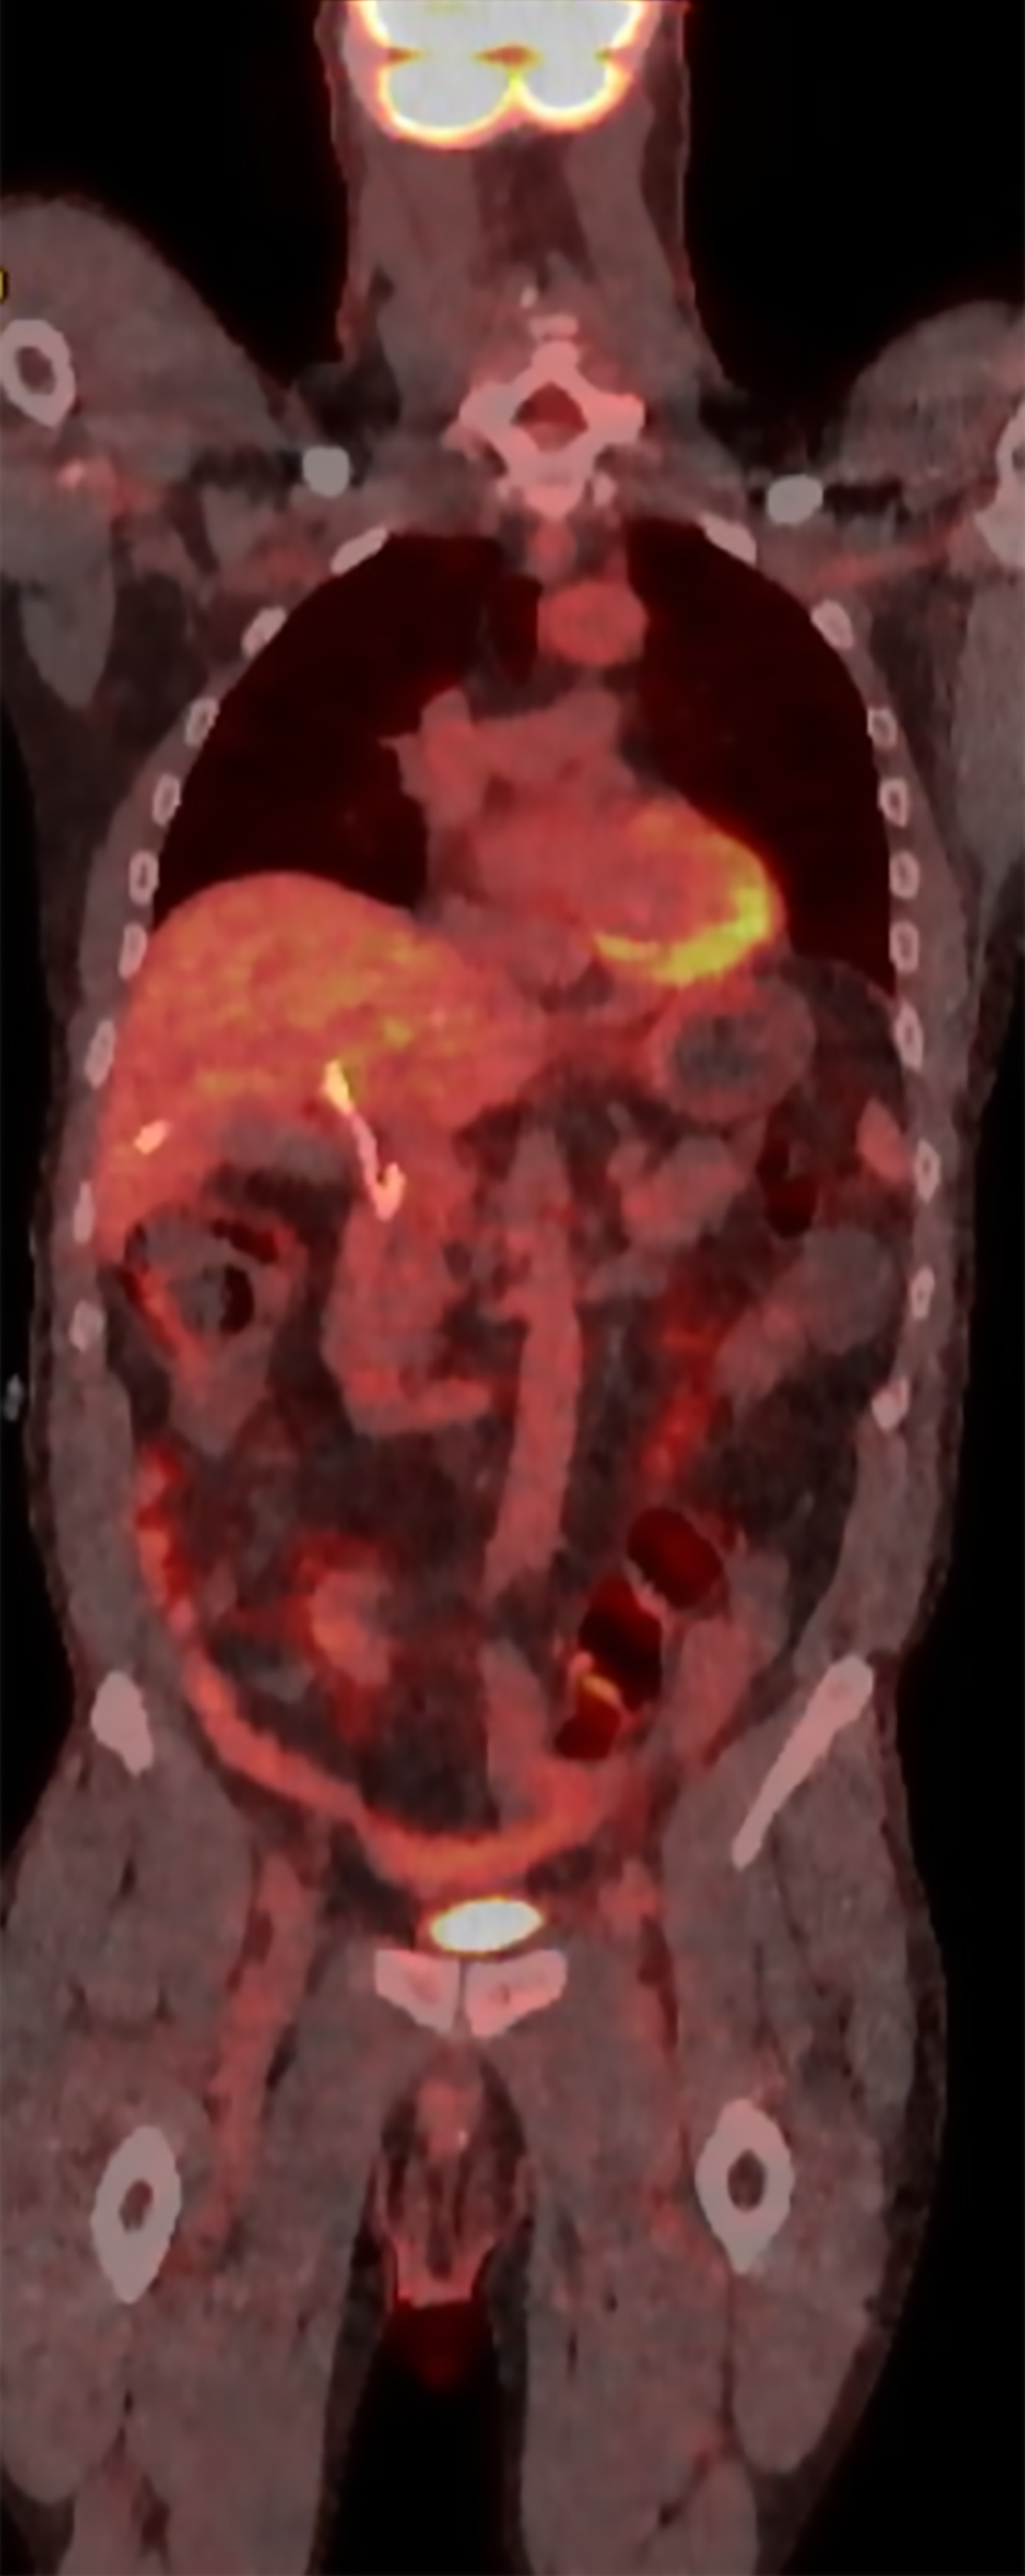

A positron emission tomography-CT (PET-CT) scan was performed after discharge that revealed no definitive fluorodeoxyglucose PET/CT evidence of malignancy. There was no abnormal activity elsewhere including the bowel and prior surgical sites and no lymphadenopathy was noted (Figure 4). Mucinous implants to the hilum from colorectal malignancy could have been a possible differential in this case given the presentation. However, there was no evidence of any ascites or features of peritoneal carcinomatosis on any of the imaging studies he underwent.

Use of imaging modalities is certainly challenging including PET-CT scan. There can be limitations in the use of PET-CT as the uptake of cholangiocarcinoma is reported to be variable and challenging to determine abnormal uptake due to physiologic excretion of tracer in the normal hepatic parenchyma. The drain which was already present in the case of our patient also further complicated the evaluation in this region. PET-CT itself can have varying sensitivity for evaluating liver metastasis which can be significantly reduced for lesions < 1.5 cm[13]. PET-CT can face other challenges as well as compared to modalities such as PET-MR when evaluating the hepatobiliary system due to the high glucose metabolism of the liver, the variable activity of tumors and quality of images[13,14].